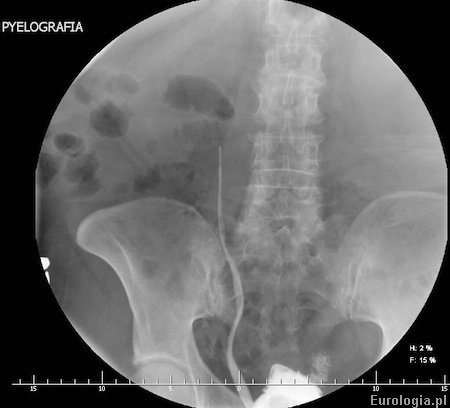

Fot. Pielografia wstępująca prawego moczowodu u pacjenta z rakiem urothelialnym moczowodu.

Pielografia wstępująca jest badaniem stosunkowo bezpiecznym i nie wymaga znieczulenia pacjenta. Pacjenci z alergią na środki kontrastujące stosowane w radiologii mogą mieć wykonywaną pielografię wstępującą bez specjalnego przygotowania. Na zdjęciu powyżej widoczne jest zdjęcie rentgenowskie wykonane podczas pielografii wstępującej u pacjenta z rakiem prawego moczowodu - widoczny jest stop kontrastu w miejscu rozrostu nowotworowego.